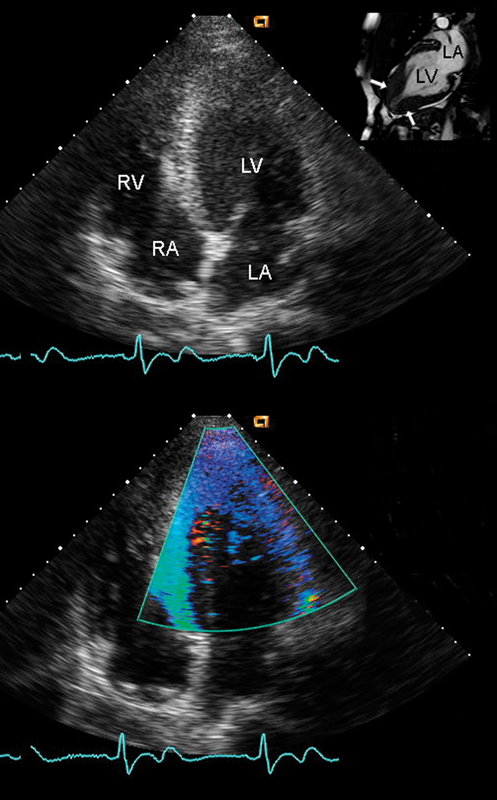

فحوصات تشخيصية لبعض امراض القلب والشرايين التاجية